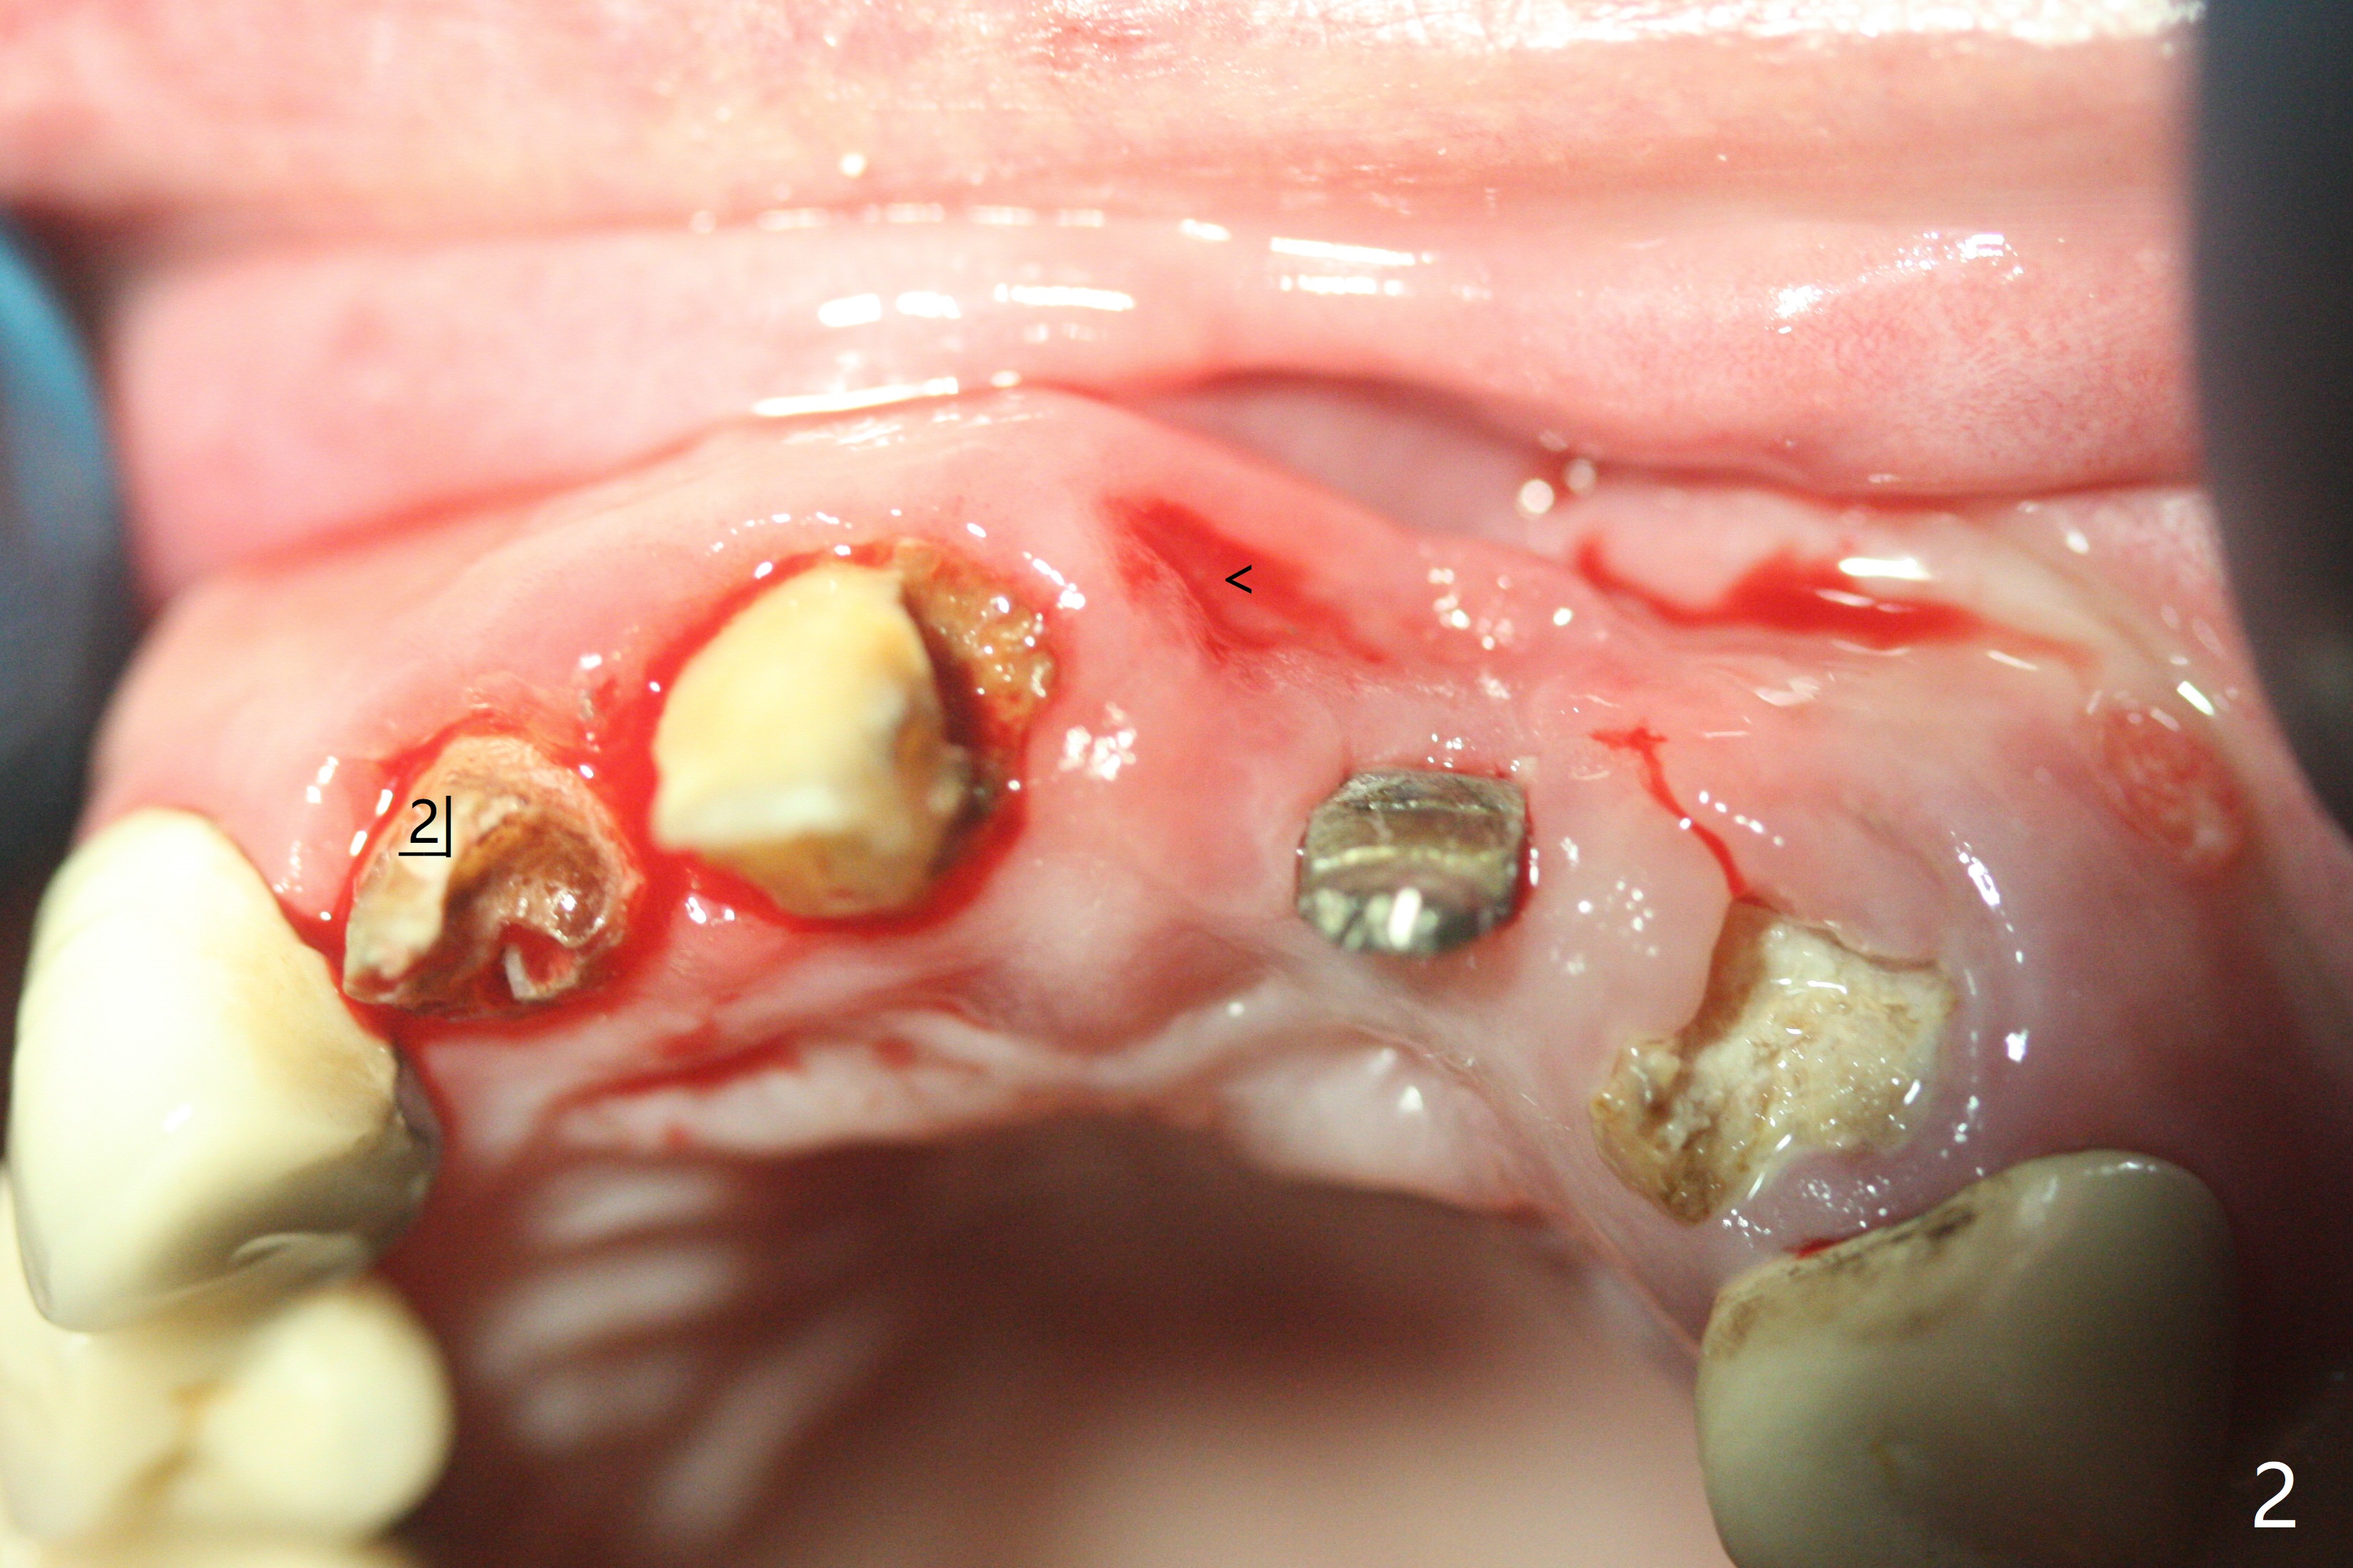

上前牙桥撤除显示右上1,2牙齿以及左上2叶片状植体好像可以保留,而左上3牙齿不能(图一,二(<:托牙边缘压迹)),拔除左上3牙齿后, 暂时把牙桥回位(图三:FPD(已经去除左上3号牙牙冠))作为3号牙种植位置参考(图四至六(G:骨粉))。其实植入前,当最后一个钻头还在原位,将PRF膜和粘性骨放置颊侧根尖(但愿骨粉能放深点),因为那里骨质很薄,好像缺损。由于植体扭力很低(大约5Ncm),放置骨粉覆盖植体(图七),为了不用缝线,涂牙周胶水(图八),放置胶原膜(图九),再涂胶水(图十)固定,最后利用右上1,2号牙(去龋,build-up后)和左上2植体制作临时牙桥,并且覆盖左上3牙槽窝。术后即刻CT显示植体颊侧(B)骨粉(图十一:*)。<:植体根尖仍有间隙,植体应该再长2毫米,初步稳定性会好些。左上3植牙愈合后,将与左上2植体制作左上1-3悬臂桥,右上1,2号牙将做根管治疗,桩,牙冠。临时牙桥术后十一天松动,右上一,二牙牙髓活性测定正常,深洗后,再次build up,不小心把左上3胶原膜吹掉,下面骨粉还稳定。术后三周病人回来做右上六种植,前牙临时修复体(图十二)需要修改(图十三)。拍摄三个方向照片显示前牙牙龈乳头(颊侧和咬合面)。